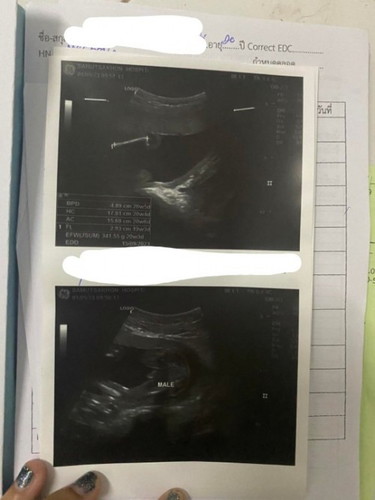

หมอบอกได้ผู้ชายค่ะ ในใบซาวด์เป็นผู้ชายใช่ไหมคะ

ภาพล่างค่ะ เห็นไข่ย้อยลงหว่างขาเลย จู๋ชี้อยู่บนตัวหนังสือเลยค่ะ

ใช่ค่ะ Male ผู้ชายค่ะ